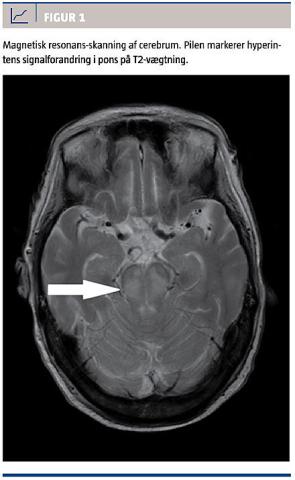

Symptomerne på EPM er akinesi, ataksi, katatoni, desorientering, dysartri, dystoni, ekstrapyramidale symptomer, emotionel labilitet, parkinsonisme, myokloni, rigiditet, tremor m.m. CPM-symptomer er pseudobulbær lammelse, quadriparese, quadriplegi, svaghed i tunge og ansigt, tab af tale- og synkeevne, psykiatriske forstyrrelser, bevidsthedsforstyrrelser, dysartri, dysfasi, spastisk paraparese, tetraparese, epileptiske anfald, hypotension og i ekstreme tilfælde locked-in-syndrom. Oftest er der symptomer på CPM med eller uden EPM [1, 2, 10]. Forløbet er ofte bifasisk med neurologiske symptomer på grund af hyponatriæmi, bedring ved korrektion og derefter forværring efter få dage. Forandringerne er først synlige på magnetisk resonans (MR)-skanning efter 2-4 uger, hvor man kan se hyperintense T2-vægtede billeder (se Figur 1 som eksempel) og hypointense T1-vægtede billeder (T2-vægtede billeder fremhæver den transverselle magnetisering, hvor T1-vægtning fremhæver den longitudinale). Den egentlige diagnose stilles ud fra symptomer, forandringer set på MR-skanning og udelukkelse af anden metabolisk/cerebral årsag.